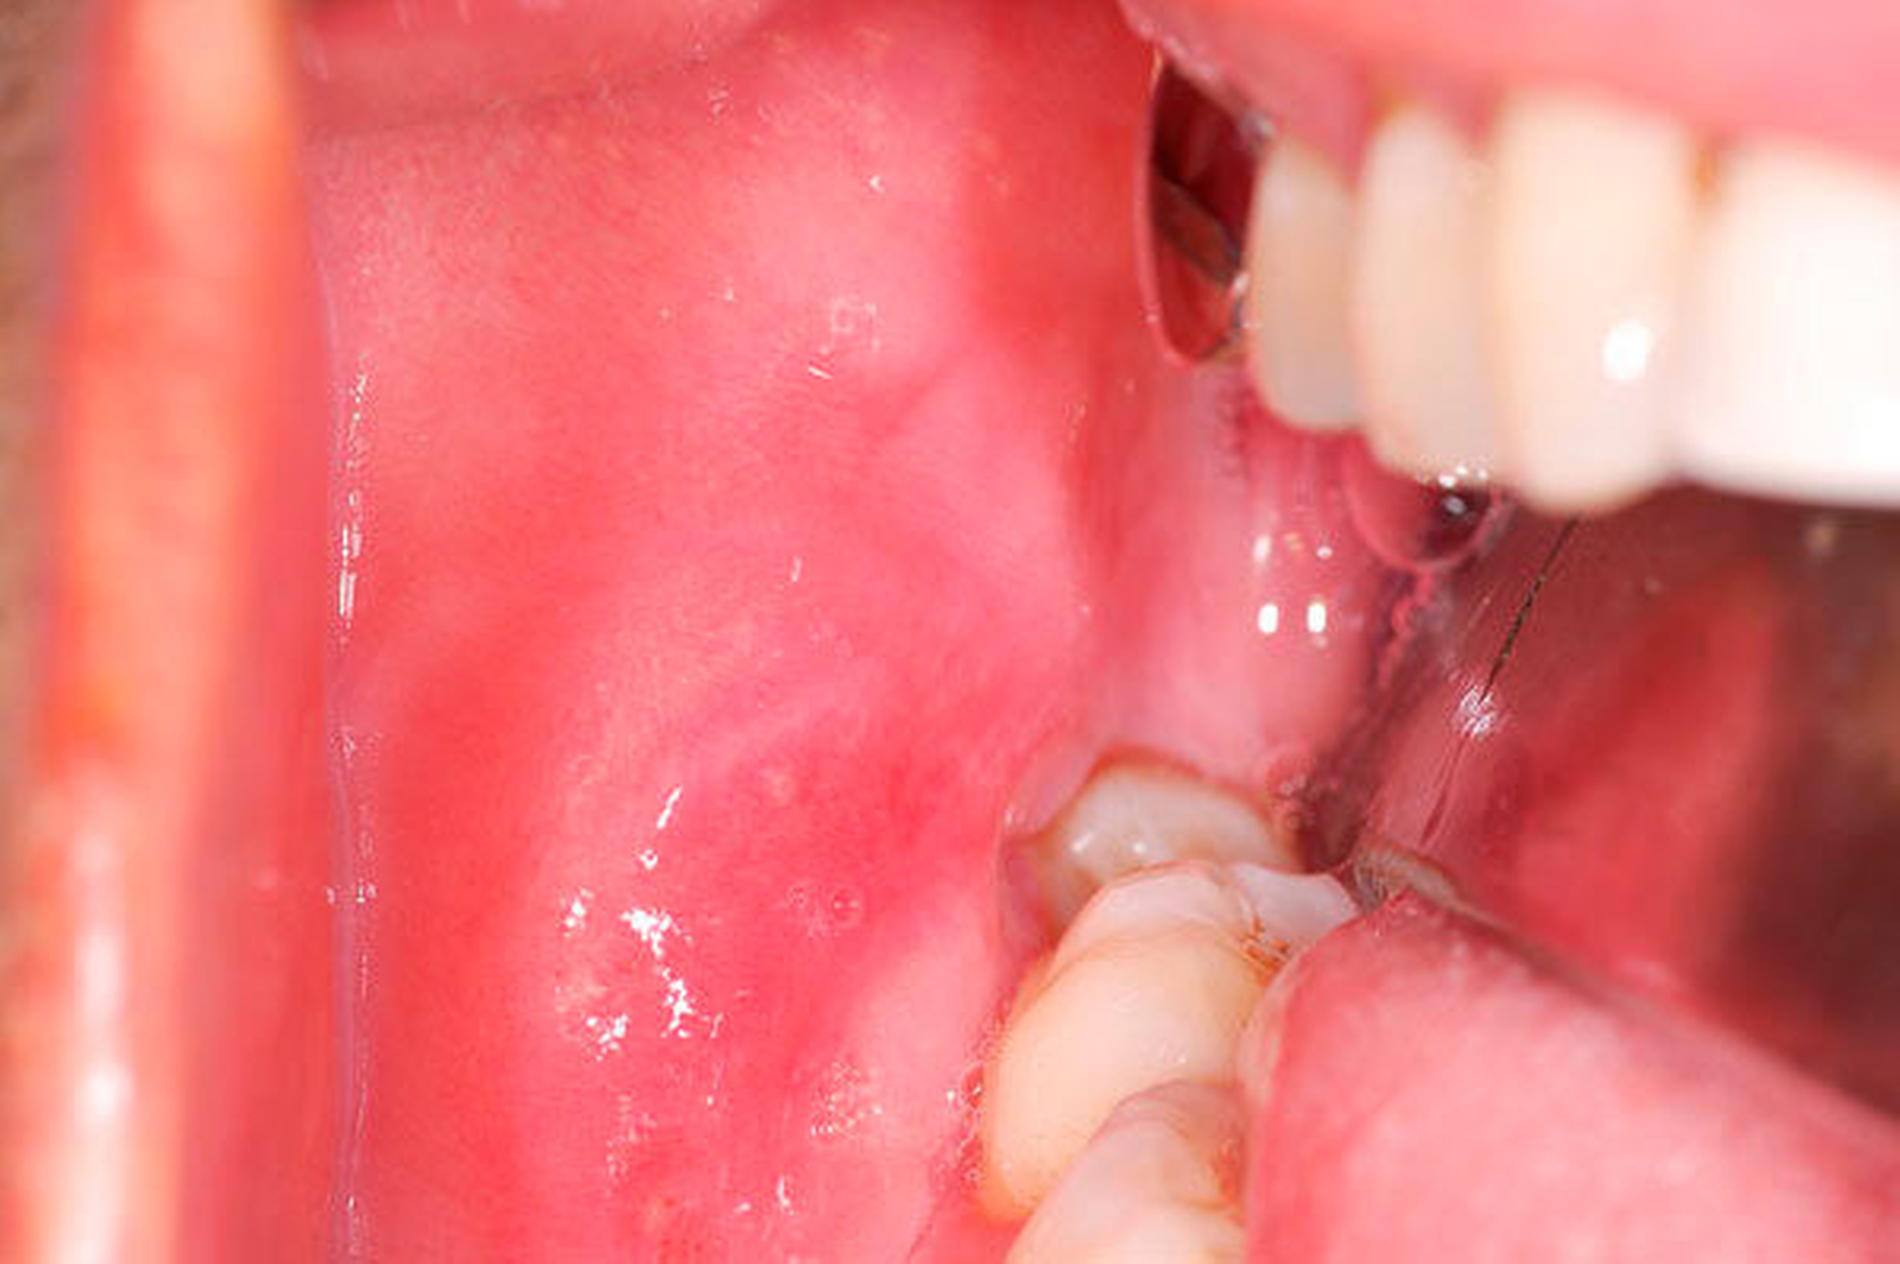

Bei der intraoralen klinischen Untersuchung erschien die Schleimhaut im rechten Unterkieferbereich nach der Probeexzision reizlos verheilt. Es zeigte sich eine nur diskrete, aber derbe Schwellung der Schleimhaut vor allem bukkal, vestibulär und koronal des nach mesial gekippten Zahnes 48 (Abbildung 2). Die Zähne 47 und 48 waren zweit- bis drittgradig gelockert. Alle Zähne des vierten Quadranten reagierten sensibel auf Kälte und zeigten sich im Perkussionstest negativ. In der computertomografischen Untersuchung stellte sich die Raumforderung vor allem im Bereich der Wange und den Zahn 48 umschließend dar. Im Bereich der Osteolyse zeigte sich die linguale, aber vor allem die vestibuläre Kortikalis ausgedünnt.